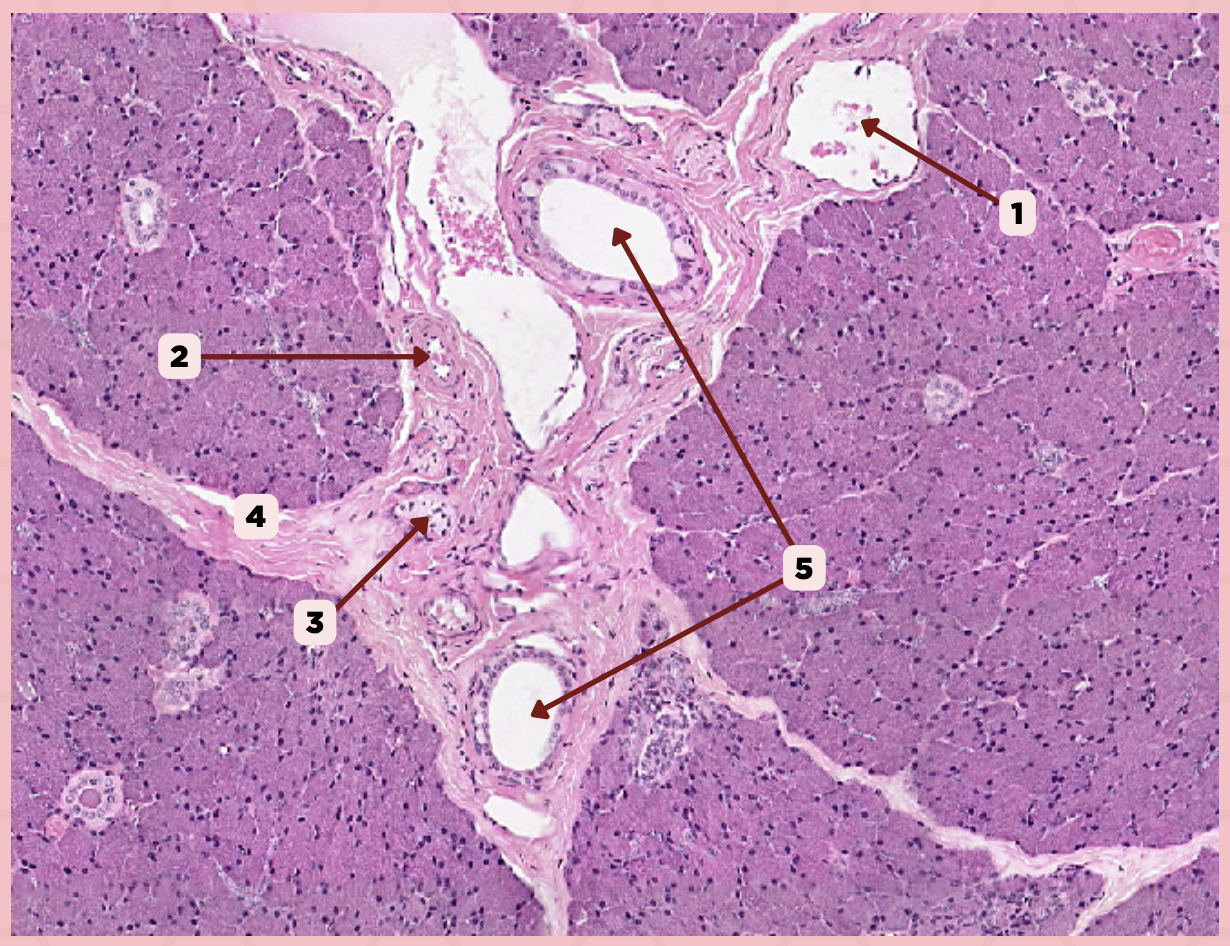

Parotid

Identify the specimen.

Vein

Identify the structure labeled as 1.

Artery

Identify the structure labeled as 2.

Nerve

Identify the structure labeled as 3.

Interlobular Septa

Identify the structure labeled as 4.

Interlobular Duct

Identify the structure labeled as 5.